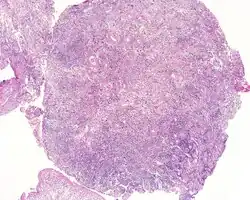

An intermediate magnification of a H&E stained biopsy from an otic polyp.

By microscopic exam, the polypoid appearance is maintained, showing a granulation-type tissue reaction with edematous stroma and a rich investment by capillaries. The surface of the polyp is covered by stratified squamous epithelium with a prominent granular cell layer. The tissue is filled with lymphocytes, plasma cells, mast cells, histiocytes, and eosinophils. It is not uncommon to see plasma cells with Russell bodies and Mott cell formation. Depending on length of symptoms, multinucleated giant cells and calcifications may be seen. Other disorders may be concurrently present, especially since this is a post infectious/inflammatory disorder, and these include a cholesterol granuloma, "tunnel clusters" (glandular epithelial inclusions below the surface epithelium), and cholesteatoma.[3][4][5]